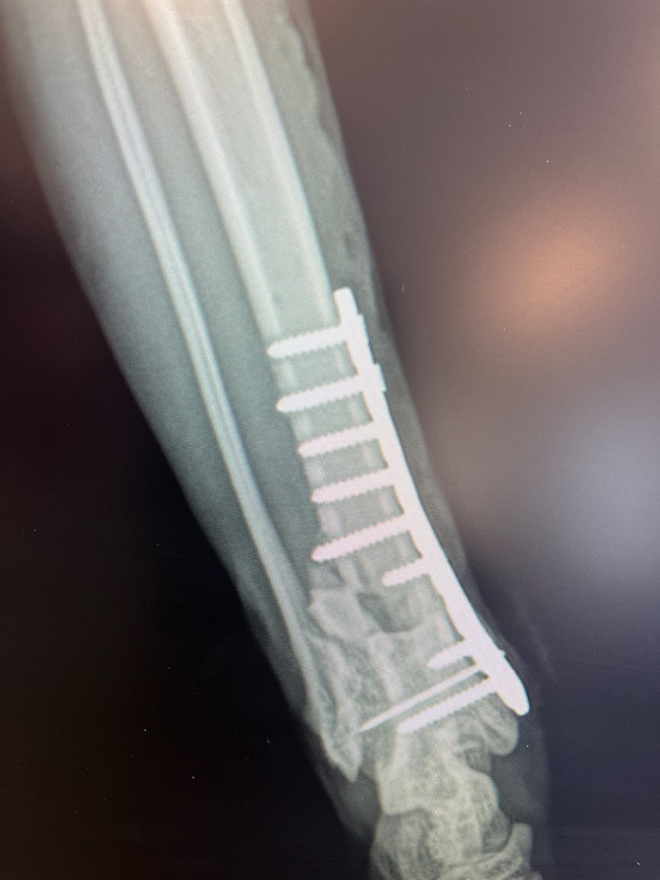

Sphinx the black cat disappeared. I was pretty much done searching and calling and crying when who should drag herself up on the deck but Sphinx. We are still not sure what happened to her but she was terribly stressed and a back leg was obviously broken.

Luckily we have a son and daughter in law who are veterinarians. So they got a call at 5:30 Friday afternoon to please stay at the clinic – Friday is usually son Todd’s day off but he had had a busy day, was still at work late and got the bad news that his mother was bringing her cat up in 2.5 hours.

A surgery and 4 weeks later we got a call that we could come and pick HIM up.